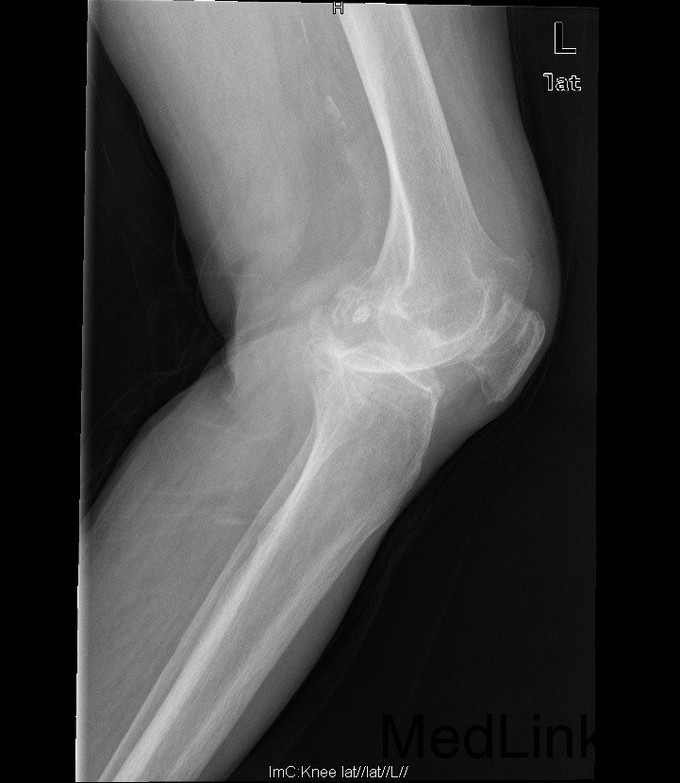

查体:查体:跛行步态,双膝关节屈曲内翻畸形,双膝内侧间隙压痛,双膝髌股关节间隙压痛,左膝伸-20°,屈110°内翻10°。右膝伸-20°,屈110°内翻10°,双膝屈伸活动时髌骨下摩擦感(+)。 辅助检查:双侧髌股关节内侧间室变窄,关节边缘骨赘增生,软骨下骨硬化。

诊断:1、双膝骨关节炎伴屈曲内翻畸形 左侧重2、高血压病(2级高危、) 治疗:在全麻下行左侧全膝关节置换术+软组织松解术,术后予以抗炎+抗凝+镇痛+补液+护胃治疗,并指导其功能锻炼。